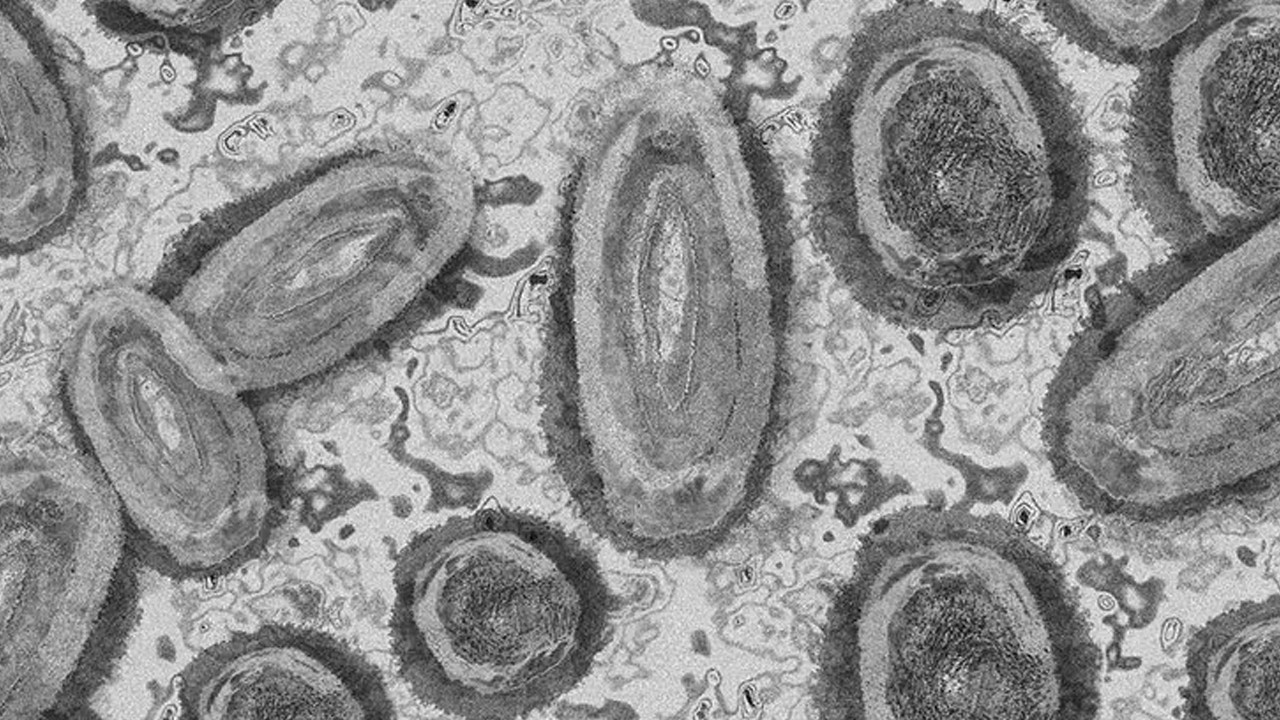

DSÖ uyardı: Afrika'da "M çiçeği" vakalarında artış yaşanıyor

Dünya Sağlık Örgütü (DSÖ), Afrika'da "M çiçeği (mpox)" vakalarında yaşanan artışa karşı uyararak bunun temel nedenlerinin belirlenmesi için yoğun araştırılmaların yapılması çağrısında bulundu.

Lewis, M çiçeği vakalarının artmaya devam etmesiyle bunun bir halk sağlığı tehdidi olmaya devam ettiğini vurgulayarak, yılbaşından bu yana dünya genelinde 3 bin 100'den fazla vaka rapor edildiğini söyledi.

"Yalnızca mayısta 26 ülkeden yaklaşık 600 doğrulanmış vaka DSÖ'ye bildirildi." ifadesini kullanan Lewis, özellikle Afrika'da M çiçeği vakalarında artış yaşandığını vurgulayarak bunun temel nedenlerinin tespit edilmesi için yoğun araştırmaların yapılması yönünde çağrıda bulundu.

Lewis, nisandan bu yana Güney Afrika'nın M çiçeği virüsünün bir varyantı olan "clad IIb" virüsüne bağlı 13 doğrulanmış vaka ve iki ölüm bildirildiğini belirtti.

Kongo Demokratik Cumhuriyeti'nin büyük bir salgınla karşı karşıya kalmaya devam ettiğini söyleyen Lewis, yalnızca 2024'te bildirilen 9 bin 291 M çiçeği vakasından 419'unun ölümle sonuçlandığını söyledi.

Lewis, Kongo Demokratik Cumhuriyeti'nde tespit edilen M çiçeği virüsü vakalarında ölüm oranın yaklaşık yüzde 5 olduğunu kaydetti.

Salgın nedeniyle daha çok çocukların yaşamını yitirdiğini kaydeden Lewis, Afrika'da M çiçeği vakalarında son zamanlarda görülen artışın ele alınmasının kritik bir ihtiyaç olduğunun da altını çizdi.